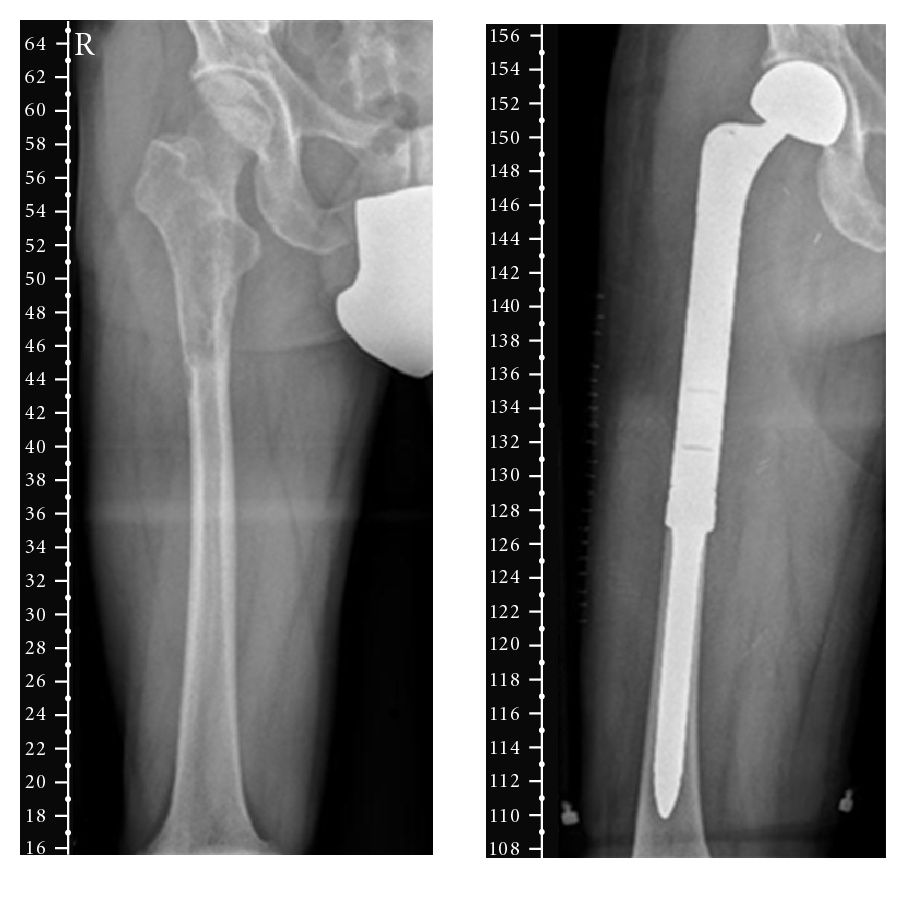

Dolor progresivo, masa palpable. Edad 40-60 años, predominio masculino (2:1). Localización: metáfisis de fémur distal, tibia proximal.

2.3 Localización

- Huesos largos (80%):

- Fémur distal (30-40%)

- Tibia proximal (15-20%)

- Localización dentro del hueso: Predominantemente metafisaria, con extensión frecuente a la epífisis y diáfisis en estadios avanzados.

10.1 Cirugía

- Resección amplia (R0): Es el estándar y el único tratamiento potencialmente curativo. Debe realizarse con márgenes de resección de 2-3 cm en hueso y 1-2 cm en partes blandas, o fascia intacta como barrera.

- Cirugía preservadora de extremidad: Posible en >90% de los casos. La planificación debe basarse en la RM preoperatoria e incluir la resección del trayecto de biopsia.